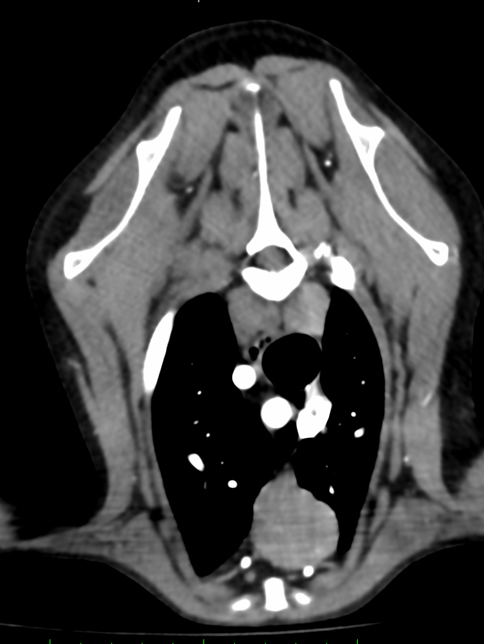

他疾患の手術前検査として実施した胸部レントゲン検査にて、前縦隔部に腫瘤性病変を認めたことから、精査のためCT検査を実施しました。 CT所見より、胸腺腫や異所性甲状腺腫瘍などの腫瘍性疾患が強く疑われたため、胸腔鏡を用いた腫瘤摘出術を行いました。 術前より臨床症状は認められず、全身状態も良好であったため、術後の経過は順調であり、術後2日目に退院となりました。

手術前のCT検査